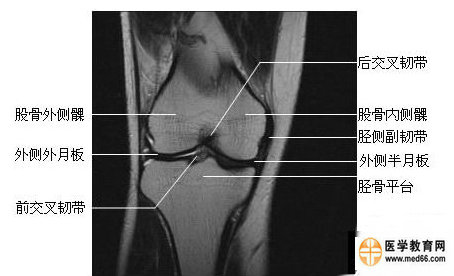

膝关节冠状面:

膝关节冠状面图